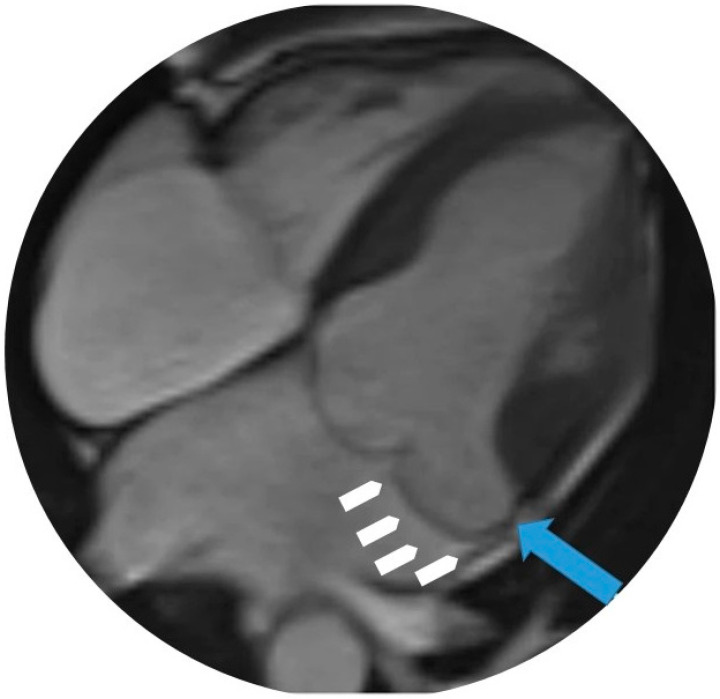

二尖瓣环分离(MAD)是一种越来越被认可的二尖瓣结构异常,通常与二尖瓣脱垂和室性心律失常和心源性猝死的风险增加有关。它是由二尖瓣环和左心室心肌之间的分离来定义的,在收缩期最明显。在这篇综述中,我们从最近的大规模影像学研究、专家共识文件和新提出的分类(如真与伪MAD)中,对MAD进行了更新和全面的概述。我们讨论了它的患病率、解剖特征和多种成像方式的诊断挑战,包括经胸和经食管超声心动图、心血管磁共振和计算机断层扫描。我们还探讨了其在心律失常发生中的病理生理作用,其预后意义和当前的管理策略。特别关注基于影像学和心律发现的风险分层,我们提出了一个实用的临床框架来指导决策。本综述旨在支持临床医生认识到MAD是一种潜在的致心律失常疾病,需要系统的评估和随访。

Mitral annular disjunction (MAD) is an increasingly recognized structural abnormality of the mitral valve apparatus, often associated with mitral valve prolapse and a heightened risk of ventricular arrhythmias and sudden cardiac death. It is defined by a separation between the mitral annulus and the left ventricular myocardium, best visualized during systole. In this review, we present an updated and comprehensive overview of MAD, drawing from recent large-scale imaging studies, expert consensus documents, and newly proposed classifications such as true versus pseudo-MAD. We discuss its prevalence, anatomical features, and diagnostic challenges across multiple imaging modalities, including transthoracic and transesophageal echocardiography, cardiovascular magnetic resonance, and computed tomography. We also explore its pathophysiological role in arrhythmogenesis, its prognostic implications, and current management strategies. Special attention is given to risk stratification based on imaging and cardiac rhythm findings, and we propose a practical clinical framework to guide decision-making. This review aims to support clinicians in recognizing MAD as a potentially arrhythmogenic condition that requires systematic evaluation and follow-up.